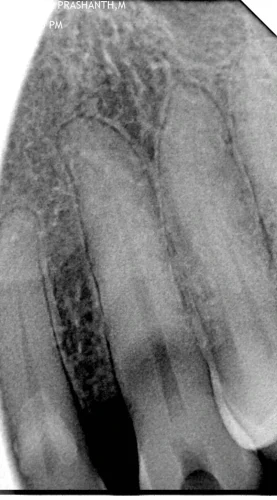

The patient reported pain and food lodgement in the lower right second premolar. No significant medical history. Due to a busy schedule, he chose Magnum Clinic for quick, expert care. The goal was to relieve pain & save the tooth via endodontic treatment.

The treatment was initiated by the use of topical anesthesia followed by the use of local anesthetic using sterilised dental syringe. A rubber dam was used to isolate the tooth to create a sterile field. Due to the presence of a calcified pulp chamber and small canals, the access cavity was meticulously prepared during a first visit of 60 minutes, which involved the debridement of the nerve as well as partial biomechanical preparation.

- Day 1- consultation which includes the IOPAR followed by the initiation of the root canal treatment( access cavity preparation , partial BMP and placement of an intracanal medicament)